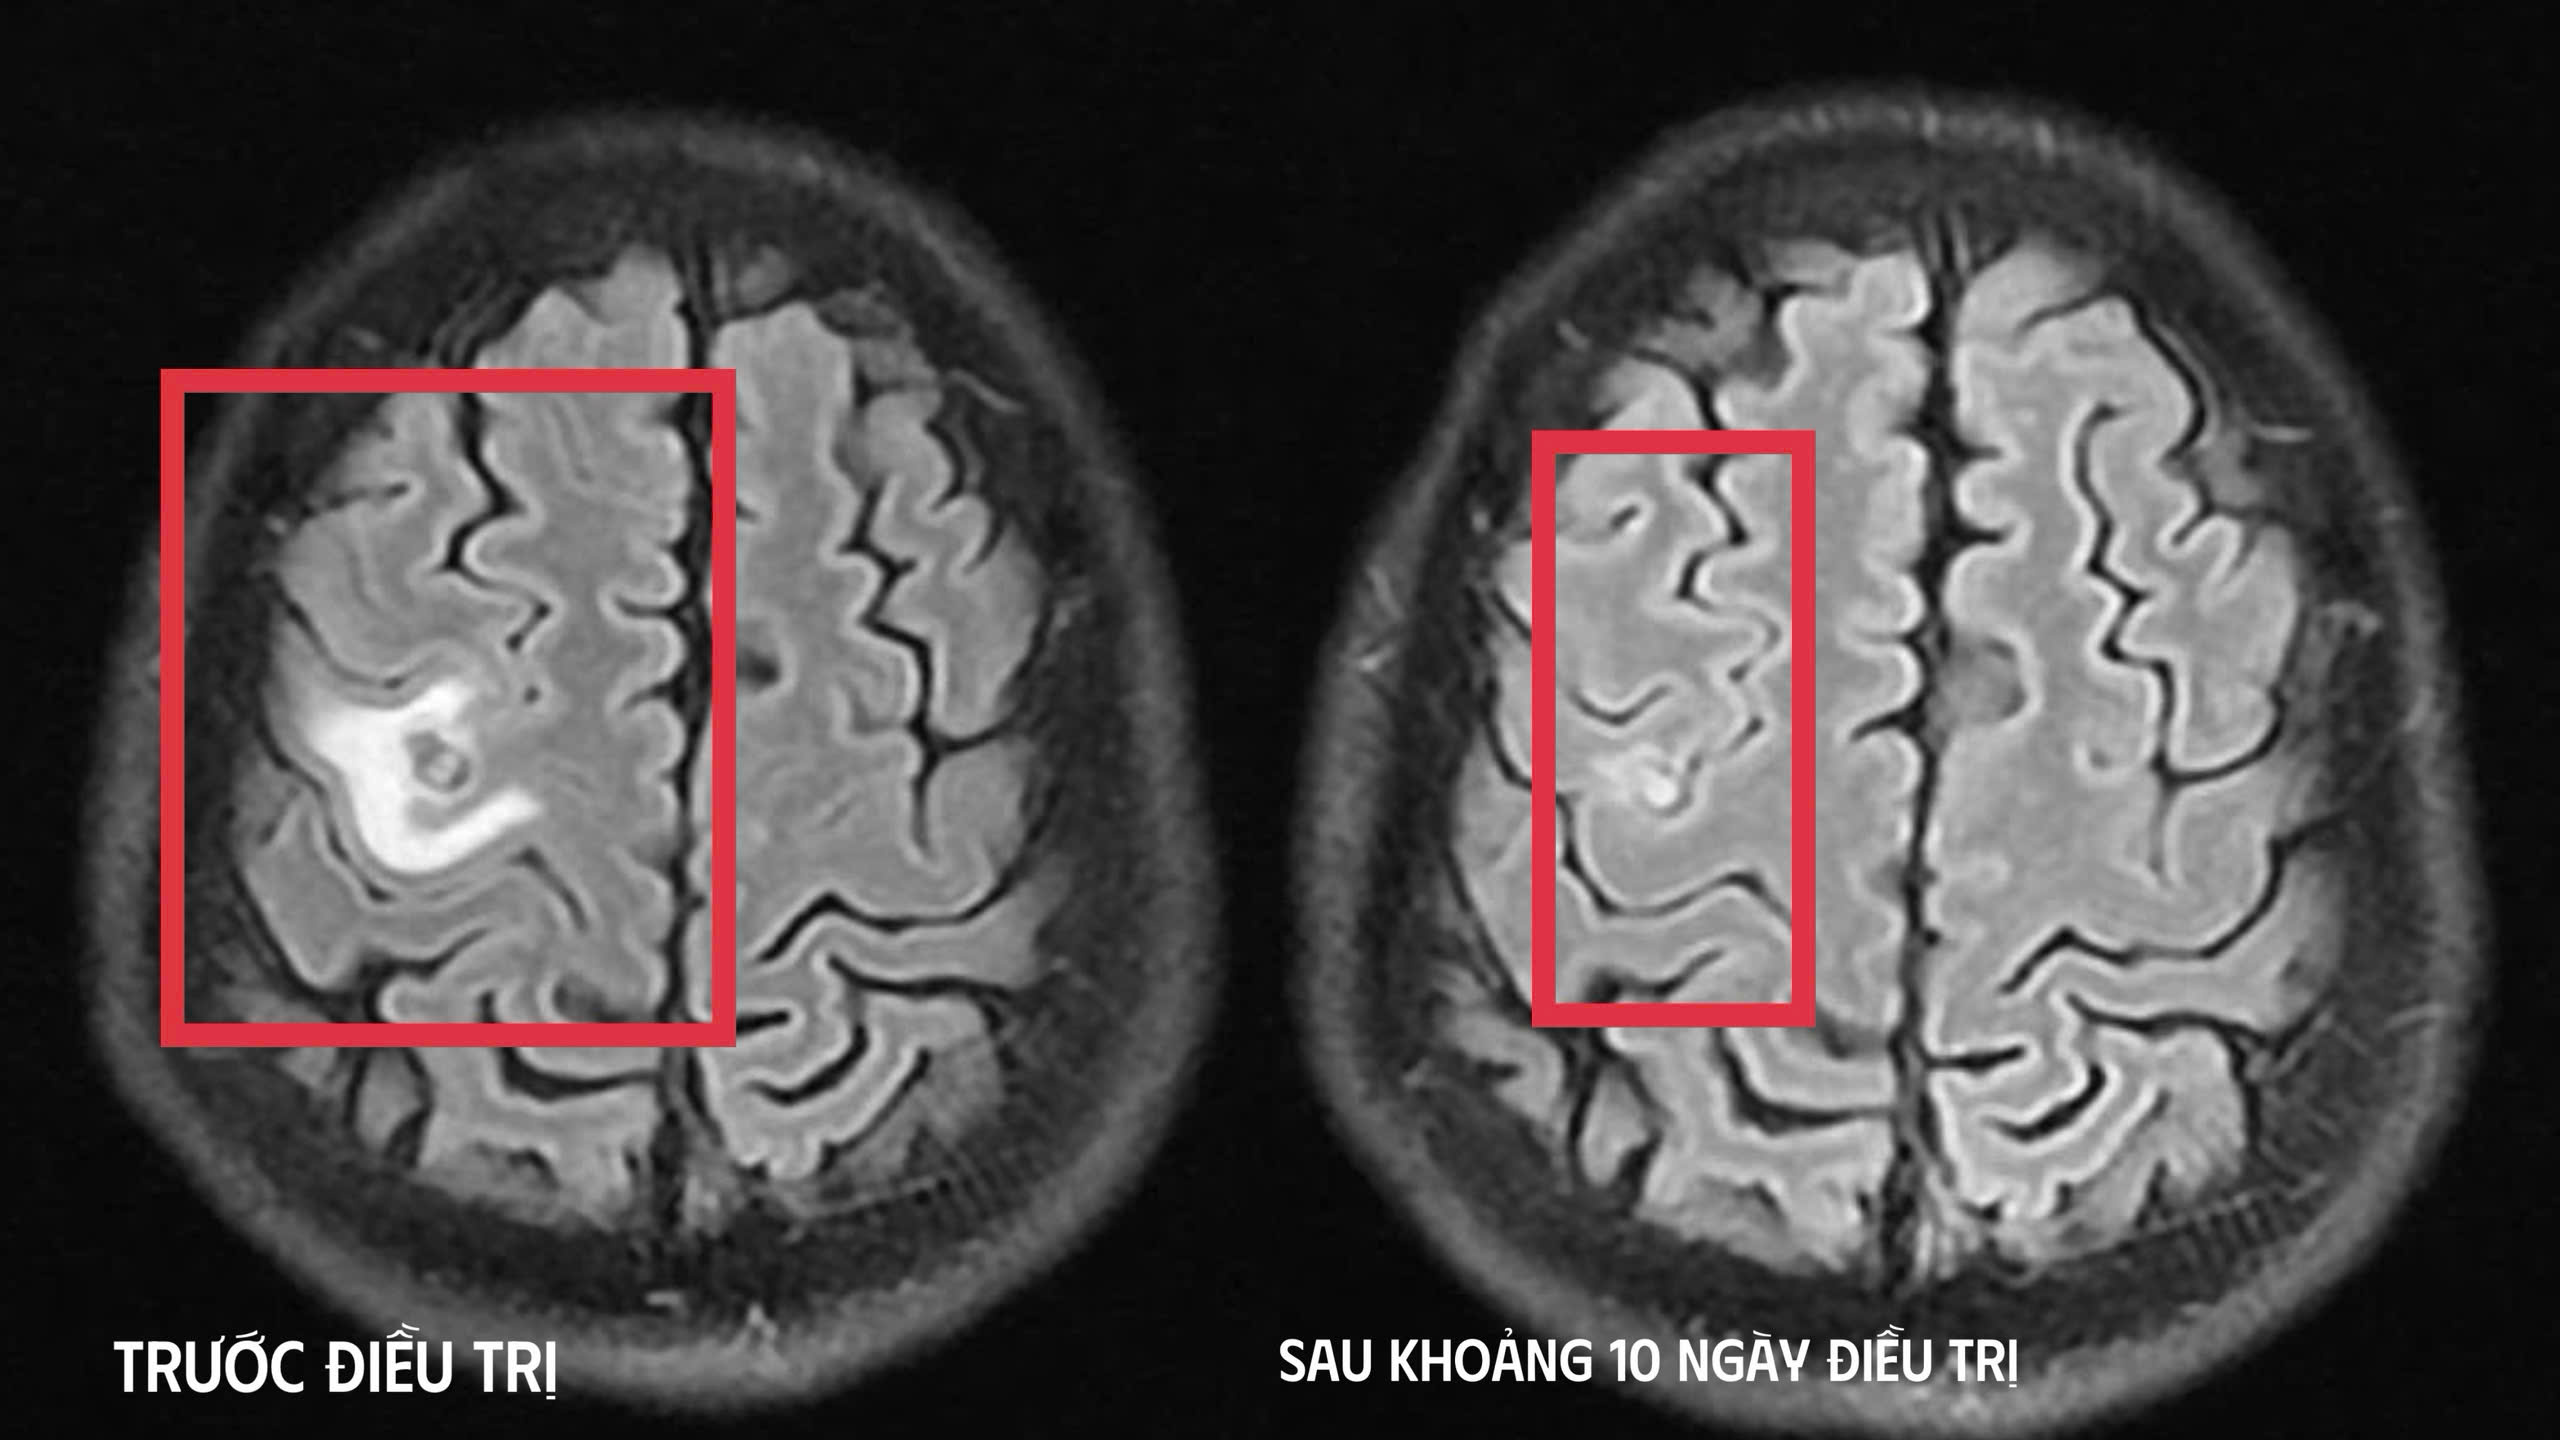

Kết quả chụp cộng hưởng từ (MRI) sọ não, phát hiện tổn thương dạng nang nhỏ tại thùy trán trái, kích thước khoảng 11x7mm, xung quanh có phù não nhẹ. Theo các bác sĩ, hình ảnh này hướng nhiều đến tổn thương do ký sinh trùng hơn là u não nguyên phát. Bệnh nhân tiếp tục được chỉ định xét nghiệm kháng thể kháng sán dây chó cho kết quả dương tính.

Sau khi xác định nguyên nhân, bệnh nhân được điều trị nội khoa theo phác đồ, kết hợp kiểm soát triệu chứng và theo dõi sát diễn biến thần kinh. Sau khoảng 10 ngày điều trị nội trú, tình trạng bệnh nhân cải thiện rõ rệt, hết tê tay, không còn xuất hiện cơn co giật, không đau đầu hay chóng mặt, toàn trạng ổn định. Người bệnh được cho ra viện và tiếp tục điều trị ngoại trú đủ liệu trình kéo dài 4 tuần.